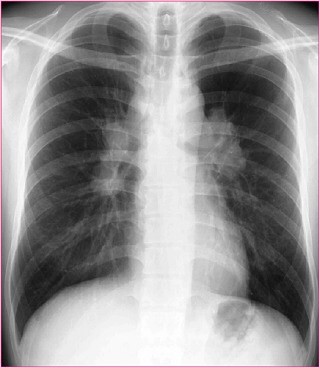

眼科でブドウマクエンと診断されて、全身検索のため内科コンサルトされた33歳男性。

下にその時の胸部レントゲン写真と組織生検写真を提示する。

この患者の肺病変に対する治療法はどれか。